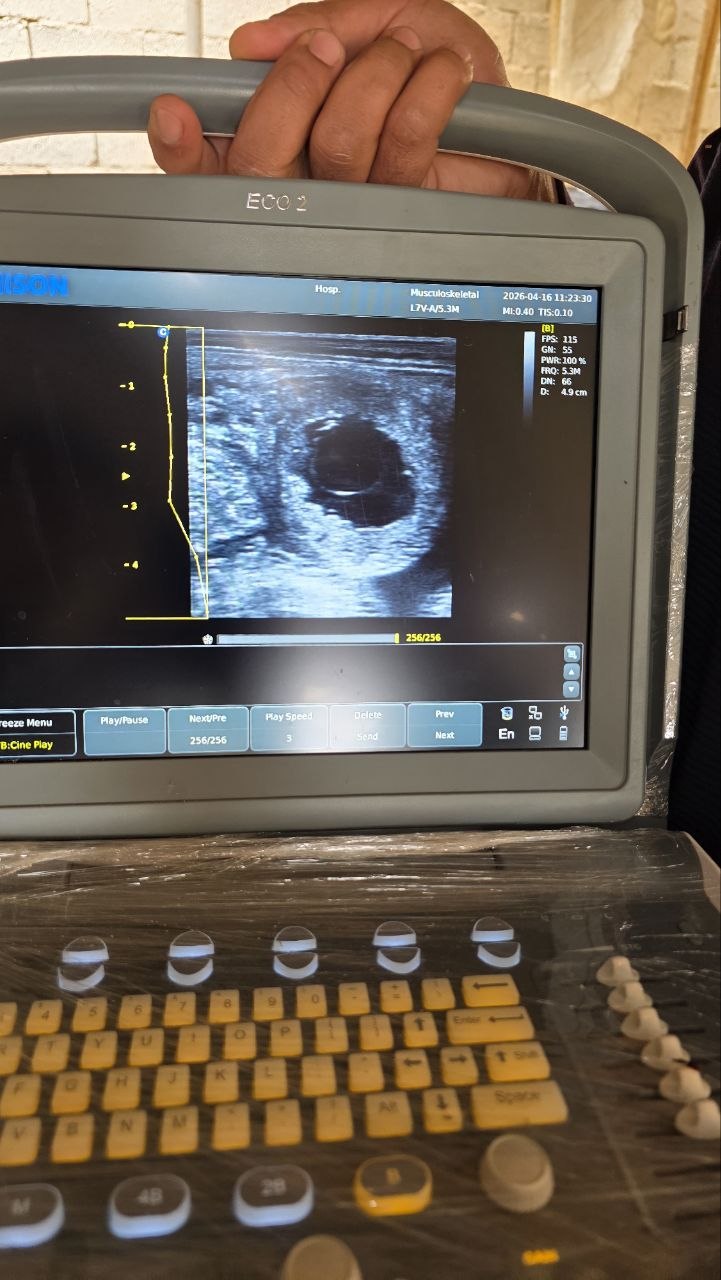

ضمن إطار تعزيز الجانب العملي وربط المعرفة النظرية بالتطبيق، قام طلاب السنة الخامسة برحلة علمية حقلية، حيث أتيحت لهم فرصة قيّمة للتعرّف على طرق الفحص والجّس باستخدام جهاز الإيكو بشكل مباشر.

أُقيمت هذه الزيارة في عيادة الدكتور عمر العبيد، حيث تعرّف الطلاب على آلية العمل في الحقل واكتسبوا خبرة عملية في استخدام جهاز الإيكو، بإشراف كل من الدكتور أحمد جدوع والدكتور عمر العبيد، الذين قدّموا شرحًا وافيًا وتدريبًا عمليًا مميزًا.